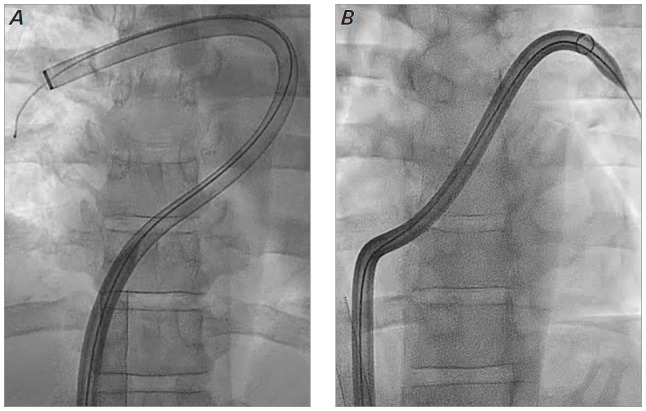

This article reports the case of a 42-year-old man who presented with a saddle pulmonary embolus complicated by normotensive cardiogenic shock. The patient was first stabilized with venoarterial extracorporeal membrane oxygenation. Then, while the patient was still on extracorporeal membrane oxygenation, thrombectomy with a large-bore catheter device was performed that resulted in a large decrease in pulmonary artery pressures and a clinically significant increase in cardiac index, with rapid clinical improvement. Complete recovery of the patient's cardiopulmonary status has been maintained at intermediate-term follow-up. This treatment strategy should be considered favorably in the treatment of patients presenting with pulmonary embolism complicated by cardiogenic shock.